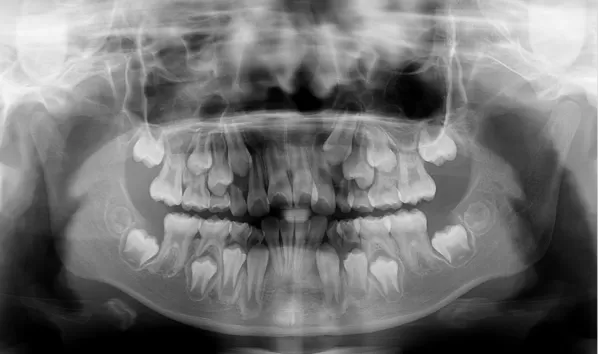

X-rays before treatment

[Panoramic Radiography/Lateral Cephalogram]